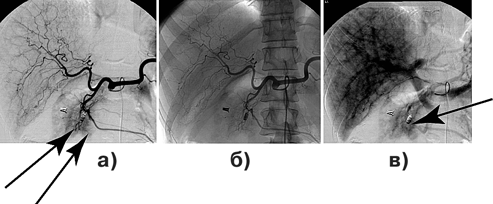

Рисунок 7. Больная Д., 44 года. Аденокарцинома перипапиллярного отдела двенадцатиперстной кишки, стенозирующая просвет кишки, состояние после формирования холецистоэнтеро- гастроэнтеро- и энтероэнтероанастомозов:

а — целиакография: артериальная фаза, зона патологических сосудов в бассейне желудочно-двенадцатиперстной артерии; б — нативный снимок: зона патологических сосудов в бассейне желудочно-двенадцатиперстной артерии; в — возвратная спленопортография: зона патологического контрастирования в проекции периампулярного отдела двенадцатиперстной кишки; г — обзорная рентгенограмма органов брюшной полости: уровень жидкости в проекции ДПК; д — то же с контрастированием бариевой взвесью: дилатация желудка, опухолевый стеноз ДПК